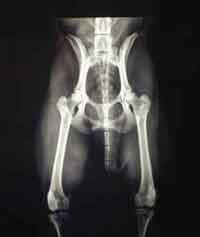

HD (Hüftgelenksdysplasie)

HD ist eine Fehlbildung der Hüftgelenke - das heißt Oberschenkelkopf und Gelenkpfanne passen nicht korrekt aufeinander. Diese Fehlbildung kann unterschiedlich ausgeprägt sein und tritt oft beidseitig auf.

Wir unterscheiden zwischen 5 verschiedenen Schweregraden der HD.

HD-frei - A

Das Gelenk ist absolut unauffällig und der Norbergwinkel beträgt 105 Grad oder mehr

HD-Verdacht/Grenzfall - B

Der Norbergwinkel beträgt 105 Grad oder mehr und die Gelenkpfanne und/oder der Schenkelkopf sind leicht ungleichmäßig oder aber Gelenkpfanne und/oder Schenkelkopf sind gleichmäßig, aber der Norbergwinkel beträgt weniger als 105 Grad

leichte HD -C

Norbergwinkel 100 Grad oder kleiner, ungleichmäßiger Oberschenkelkopf und Gelenkpfanne. Unter Umständen sind auch schon leichter arthrotischer Veränderungen zu bemerken.

mittlere HD - D

Norbergwinkel größer als 90 Grad und deutliche Ungleichmäßigkeiten von Oberschenkelkopf und Gelenkpfanne. Veränderungen des Pfannenrandes und/oder arthrotische Veränderungen sind zu erwarten oder schon vorhanden.

schwere HD - E

Norbergwinkel weniger ald 90 Grad, abgeflachter Pfannenrand, auffällige Veränderungen an Oberschenkelkopf und Gelenkpfanne. Deutliche arthrotische Veränderungen sind zu erwarten oder schon vorhanden.